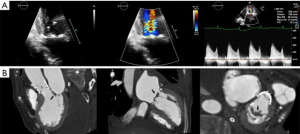

- CT, compared to echocardiography, lacks hemodynamic data, has lower signal to noise ratio, comparable temporal resolution and better spatial and contrast resolution, making it suitable for MV imaging (10). Operator-dependent, optimized imaging protocols for MV include: wide field of view, higher peak kV, bolus timing using time attenuation curves, left atrial contrast target, 5–10% phase intervals and specific reconstructions for annulus sizing and LVOT analysis (11). Image analysis is performed on the thinnest possible slice, using projections similar to echocardiographic views, with 4D reconstructions and multiplanar reformatting adjusted to minimize beam hardening and blooming effect. Lifelike, 4DCT cinematic rendering may be more useful compared to traditional 3D volumetric reconstructions. CT is indispensable for mitral annulus sizing and for the prediction and evaluation of LVOT obstruction risk in TMVR (Figure 3, Video 2) (10,12-22). Additionally, CT allows precise measurement of the geometric mitral valve area, predicts optimal fluoroscopic angles and identifies the location of the coronary sinus in relation with the annulus (Figure 4). Accurate sizing of the MA is critical for device choice. The least square planes method projects the 3D contour of the annulus on to a 2D plane and led to the concept of a simplified, flat, D-shaped mitral annulus, which reflects the actual planar landing zone of TMVR devices (6,23,24). A reproducible “effective annular diameter” can be derived from either the measured area, or the perimeter of the annulus (12). CT is vastly superior to echocardiography in imaging mitral annulus calcification (MAC), which can disrupt the atrioventricular groove and extend into the leaflets or the adjacent myocardium. Extensive leaflet calcification or fibrosis represents the basis of “degenerative MS” (Figure 5). MAC may involve the adjacent myocardium, or display a “caseous” core, without significant MS (Figure 6). TMVR creates a “neo-LVOT” between the basal segment of the interventricular septum and the AML, displaced anteriorly by the prosthesis struts, or flange (25). The semilunar cross-sectional area of the neo-LVOT may be measured by planimetry. Since LVOT obstruction may have profound hemodynamic consequences, several methods have been proposed to predict the risk of this complication, including proprietary software (11,24-26). Predictors of LVOT obstruction can be identified by CT, TTE or TEE: aorto-mitral angle <110°, LVOT area <2.0 cm2, length of the AML, short chordae, direct papillary muscle attachment, thickness of the basal segment of the interventricular septum and LV cavity size.

Valve models can be superimposed on CT images for accurate prediction of LVOT obstruction. In such cases, device alignment with the annular trajectory, adjustment of deployment height leading to variable lengths of the ventricular protrusion and intentional flaring of the ventricular aspect of the TMVR device should be considered (Figure 7). CT can identify device thrombosis or pannus, based on their different attenuation characteristics (Figure 8).